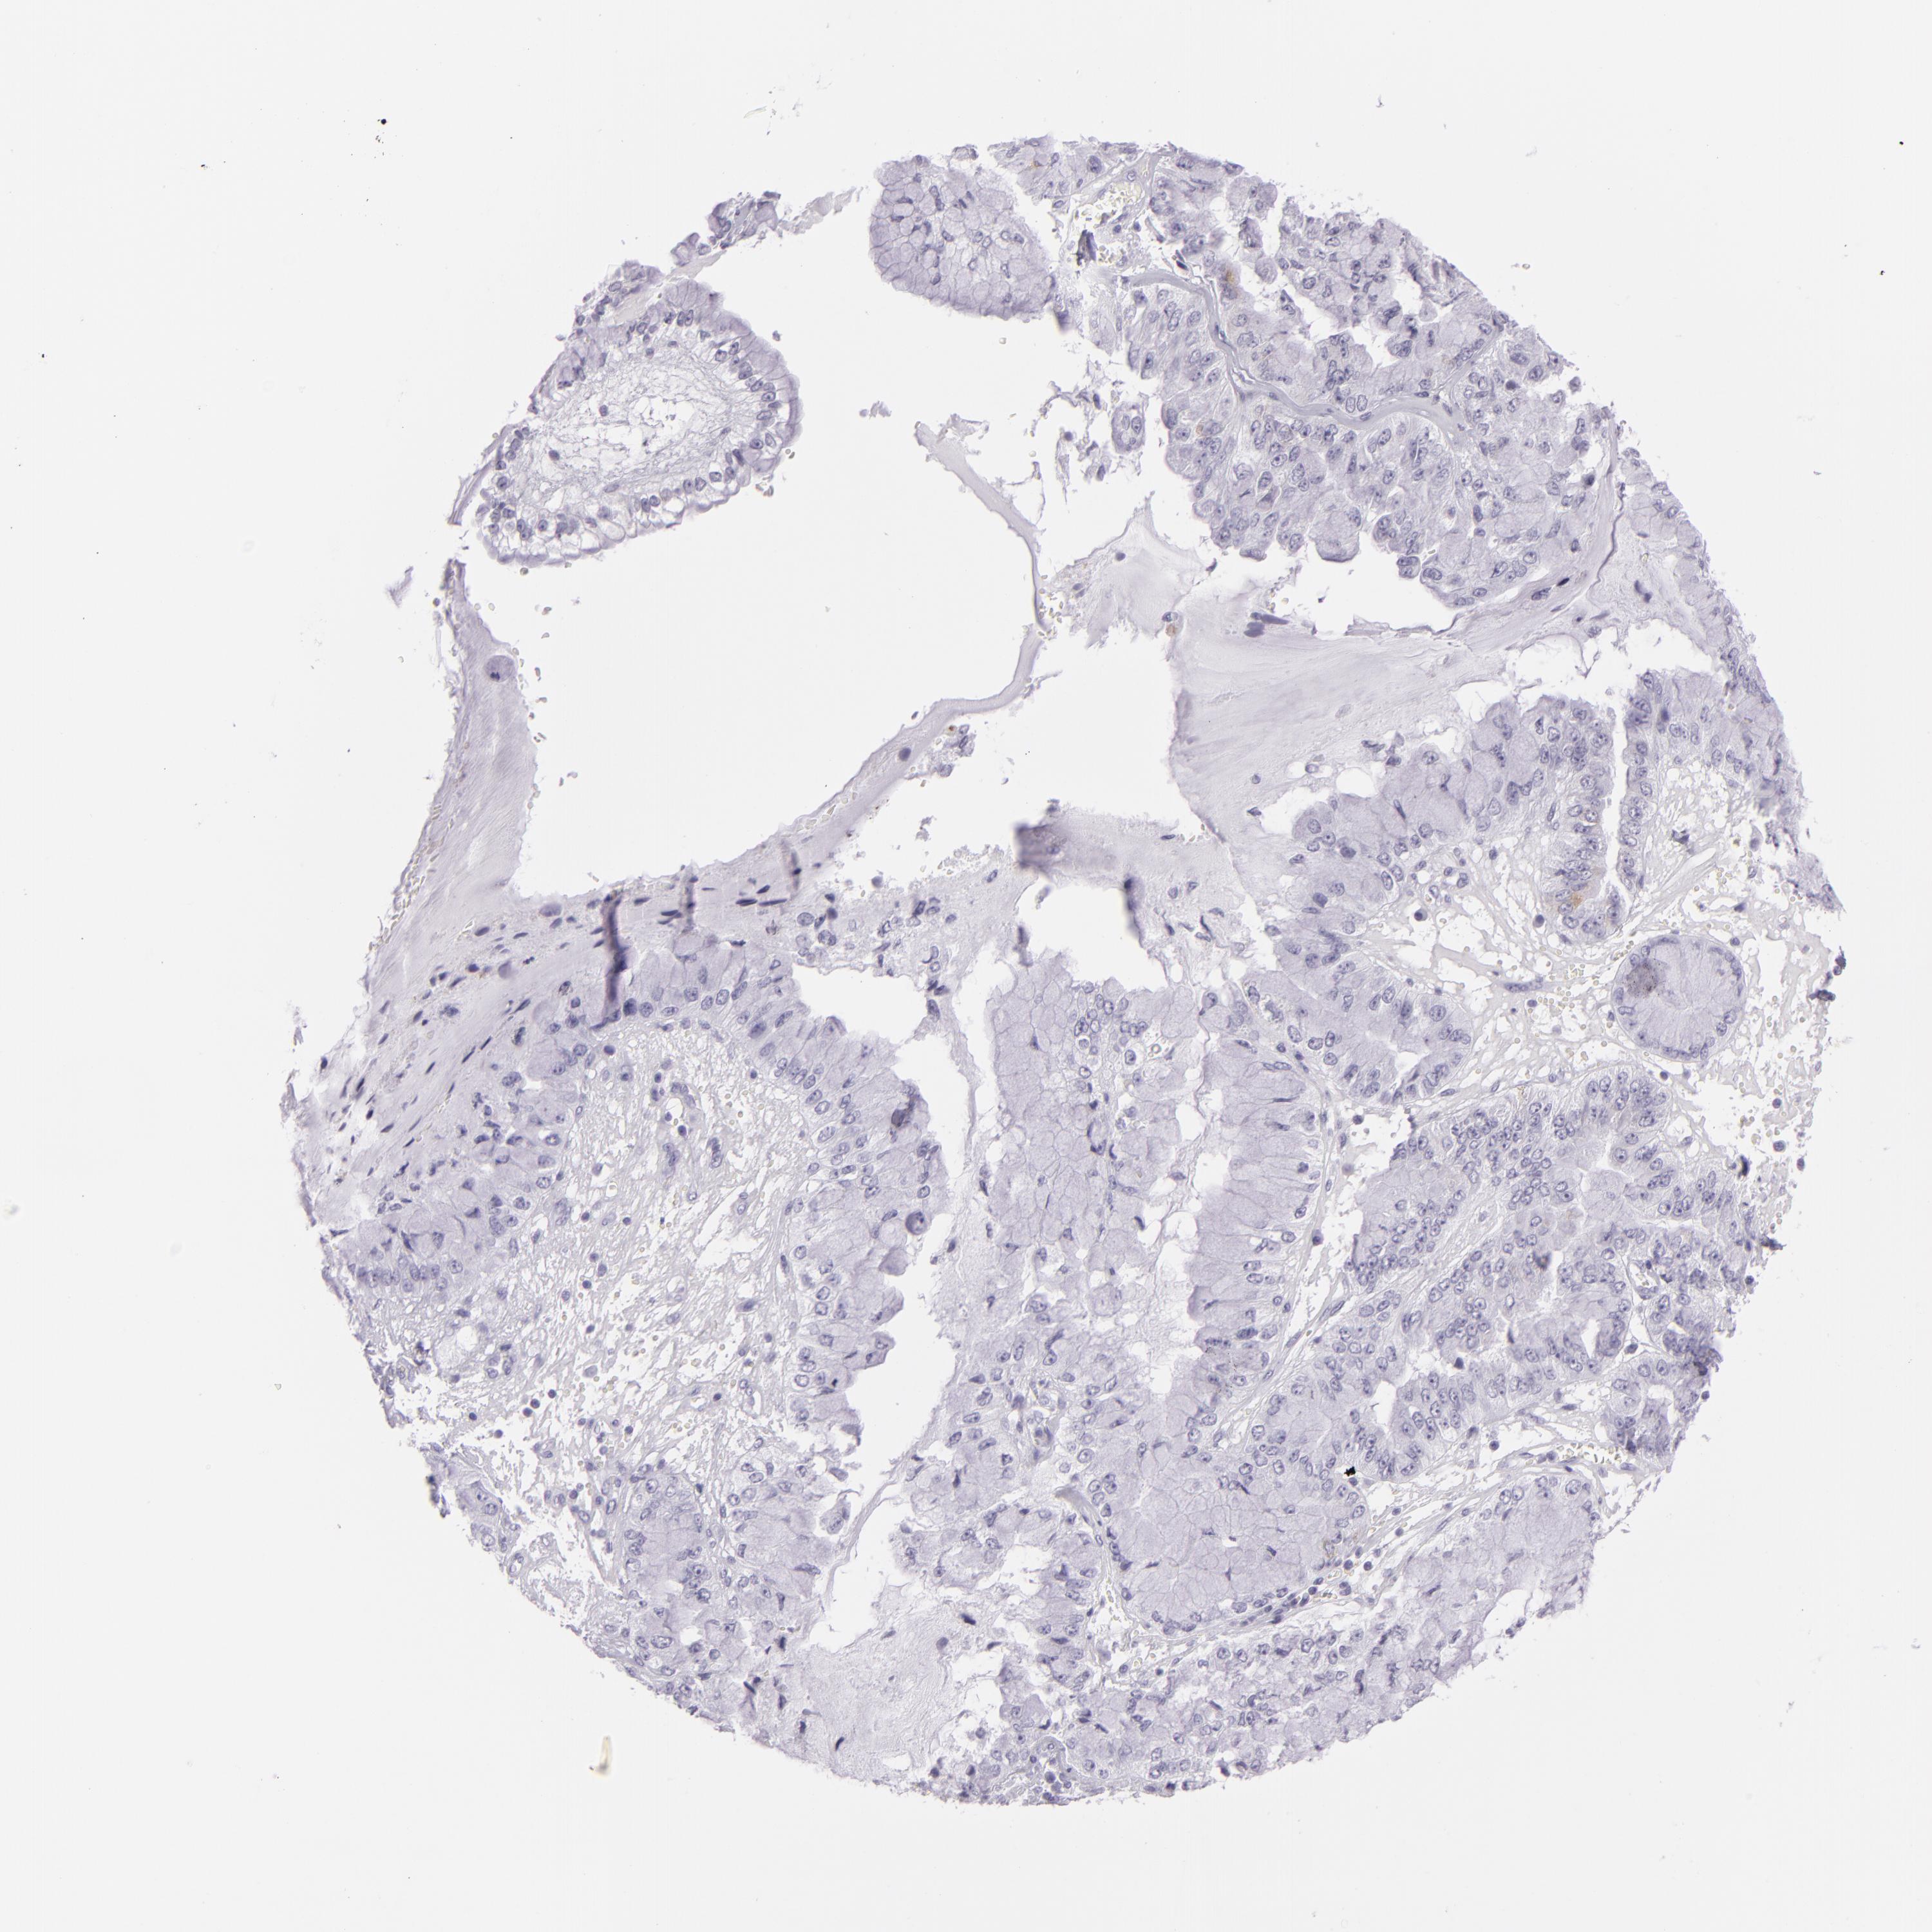

LIVER CANCER - Protein expressioni

A mouse-over function shows sample information and annotation data. Click on an image to view it in a full screen mode. Samples can be filtered based on level of antibody staining by selecting one or several of the following categories: high, medium, low and not detected. The assay and annotation is described here.

Note that samples used for immunohistochemistry by the Human Protein Atlas do not correspond to samples in the TCGA dataset.

Antibody stainingi

Antibody staining in the annotated cell types in the current human tissue is reported as not detected, low, medium, or high, based on conventional immunohistochemistry profiling in selected tissues. This score is based on the combination of the staining intensity and fraction of stained cells.

Each image is clickable and will lead to virtual microscopy that enables deeper exploration of all samples and also displays staining intensity scores, fraction scores and subcellular localization as well as patient and tissue information for each sample.

Antibody CAB002165

Staining

High

Medium

Low

Not detected

Intensity

Strong

Moderate

Weak

Negative

Quantity

>75%

75%-25%

<25%

None

Location

Nuclear

Cytoplasmic/membranous

Cytoplasmic/membranous,nuclear

Carcinoma, Hepatocellular, NOS

Cholangiocarcinoma